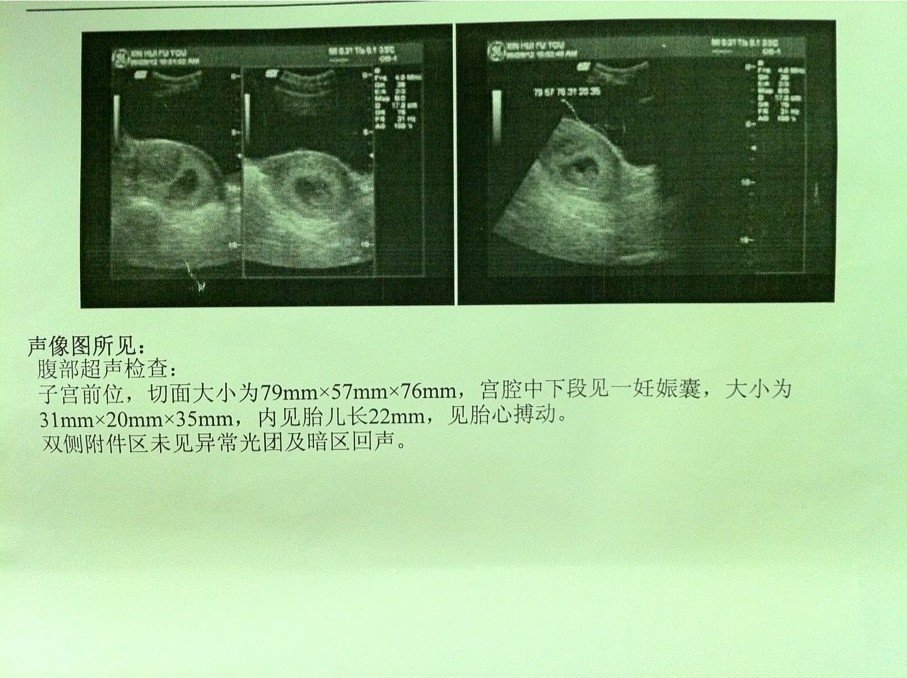

请问怀孕早期胎儿位置偏低会严重吗?我B超图显示的请问有没有问题呢? 患者信息:女 26岁 广东 江门 病情描述(发病时间、主要症状等):早一个星期有咖啡色分泌物,而且有一点点的鲜红色血滴在内裤,今天开始就开始没什么颜色了。 点击展开 匿名用户 2012-07-05 17:03 为您推荐: 其他回答 参考答案 我们都是远视眼,模糊了离我们最近的幸福 匿名用户 2014-11-24 15:11 没有胎儿位置低的说法,如果胎盘低置,随着月份增大会有流血,能保多久是多久。 扬志明_V2Uf 2012-07-05 17:53 相关问题 今天做B超,医生说胎囊位置偏低,影响胎儿发育吗 关于怀孕早期吃羊肉火锅会不会对胎儿有影响?的问题 我29号做B超胎盘位置前壁,2级有什么问题吗,这可以看出来胎儿入盆了吗,可以看出宝宝多大吗,谢谢